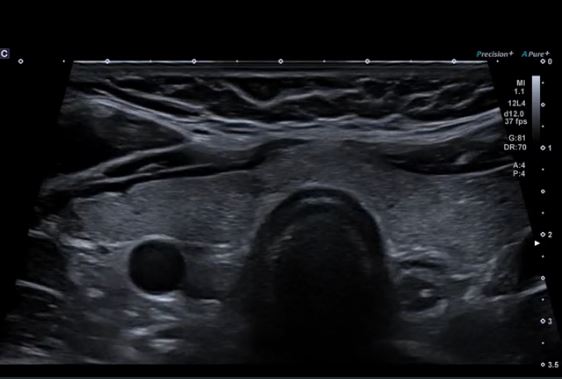

Ультра широкий огляд печінки та нирок надає більше інформації в одній площині.

Монокристалічний конвексний датчик забезпечує зображення високої роздільної здатності для абдомінальних досліджень. Висока щільність елементів у поєднанні з iBeam+ забезпечує ультрашироке поле огляду 140°, яке наразі доступне лише для Aplio i-серії.

Конвексний датчик PVU-574BT (10C1)